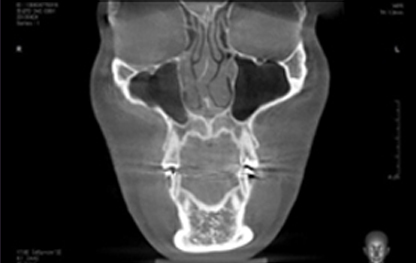

3D-CT

입체분석

을 통한

심층검사

수술 전 3D-CT 입체 분석을 통해

환자의 코 뼈는 물론 코 주변 연부 조직의

모양, 상태, 크기까지 정밀하게 검사하여

환자 개개인에 맞는 1:1 맞춤 수술을 계획합니다.

• 연골 비대칭 및

비중격 만곡증의 유무

• 하비갑개 비후 및

코막힘 문제해결

• 비중격 연골의

상태와 크기 분석

• 코 뼈의 넓이